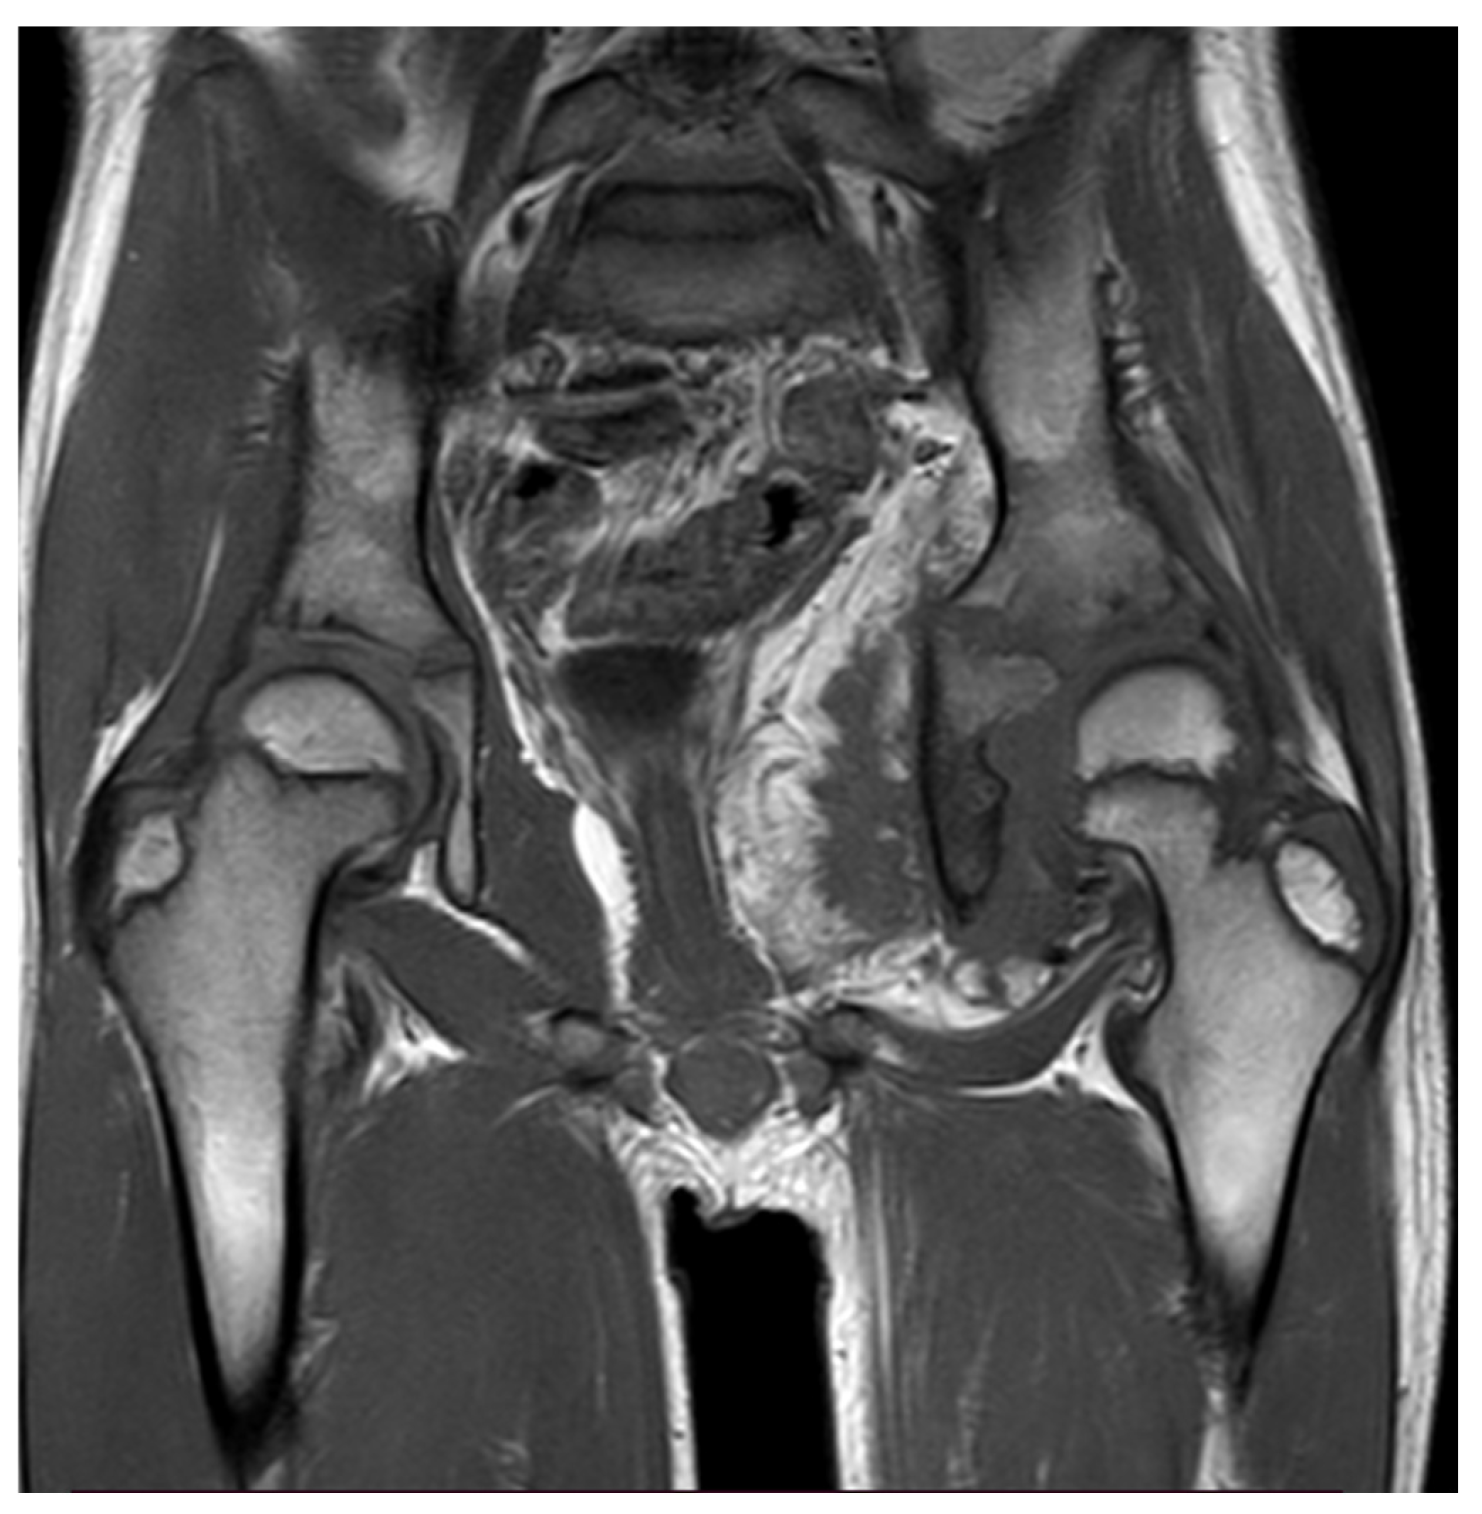

Thirteen months later, the patient underwent a new pelvis MRI examination due to the symptoms worsening and a significant decrease in the range of motion of the left hip. MRI revealed a large heterogeneous soft-tissue mass in the abdominal cavity, with extension to the hip joint, presenting both fat and muscle signal intensity with heterogeneous enhancement post gadolinium, and associated with extensive peri-osseous fatty infiltration, a reactive soft-tissue component, and advanced severe atrophy of the left obturator muscles (

Figure 1). These findings were not observed in the previous MRI.

5]. The MRI conducted on our patient showed extensive peri-osseous fatty infiltration by soft tissue reaction, which correlates with the fact that MRI shows the features of fat tissue in lipomatous components of myolipoma.